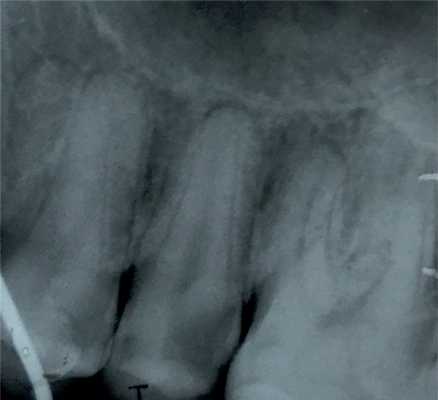

Дополнительные методы обследования: было проведено диагностическое рентгенологическое исследование. При анализе внутриротовой контактной рентгенограммы зуба 1.5 отмечался очаг разряжения костной ткани в области верхушки корня зуба 1.5 (рис. 2). Рис. 2. Внутриротовая контактная рентгенограмма зуба 1.5 до лечения. При проведении электроодонтометрии зуба 1.5 было получено значение более 100 мкА. При проведении термометрии зуб 1.5 не реагировал на холодовой и тепловой раздражители.